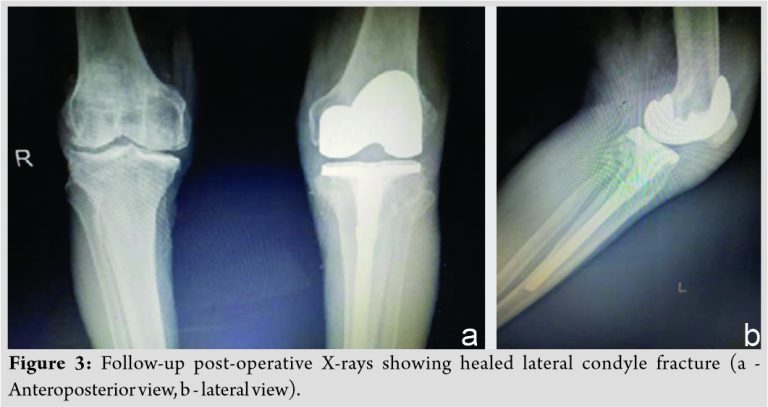

After getting the fitness for surgery (40 days after the trauma), the patient was operated in supine position through medial parapatellar approach using tourniquet. After the femur preparation, tibial preparation was started with removal of fibrous tissue at the fracture site, anatomical reduction of fracture, and maintaining the reduction with reduction forceps till the completion of the tibial preparation to prevent the displacement of fracture fragment. Cemented TKR was done using Zimmer implant of femoral component size E, tibial component of size 4 with stem extension of 12 mm diameter × 155 mm length and articular surface height of 10 mm (Fig. 2a and b). As the fracture was properly reduced to anatomical position and there was only fracture split, no depression, the augmentation was not required. Wound was closed in layers and the patient was given long knee brace postoperatively. Partial weight-bearing and knee range of motion were started after 3 days and full weight-bearing was started after 3 weeks. Eight months post-operative X-rays (Fig. 3a and b) showed healing of lateral condyle fracture and without any loosening of implants. The patient is having good knee range of movements and no pain on weight-bearing at present (Fig. 4a and b).

At present 1.2 years follow-up, the patient is comfortable with no pain and difficulty in walking. Functional outcome is good as per Oxford knee score. Shorter follow-up period is the limitation of this case report.